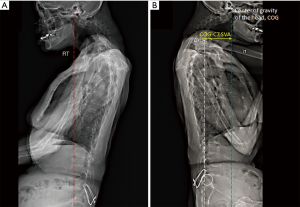

Figure 2 Postural assessment. (A) At initial assessment, the patient could not stand unaided. She supported herself with the right hand holding door handle and the back leaning against the cabin interior. Sagittal EOS® radiograph showed severe cervical kyphosis, degenerative spondylosis and s/p internal fixation of the sacrum. (B) At 4-month follow-up, sagittal EOS® imaging demonstrated cervical imbalance with respect to offset of the center of gravity of the head [COG-C7 sagittal vertical axis (SVA) offset, yellow arrow]. With straightening of the lumbar spine, the C7 plumb line (dashed white line) was tangential to the posterior-superior corner of the upper sacral endplate (white circle), suggestive of a compensated global sagittal balance. In the sagittal plane, the gravity line (dashed red line) passes slightly posterior to the hip joint.

In the absence of neurological deficits, the first phase of treatment aimed to improve neck muscle strength. Gentle mobilization of the upper thoracic spine, electrical muscle stimulation (EMS) of the cervical extensors, and home-based neck exercises for motor strengthening were prescribed. Home-based exercises included shoulder shrugs (slowly raise both shoulders up, and hold for 5 seconds), head retraction (use a couple of fingers to tuck the chin gently backwards against the neck, and hold for 5 seconds), and neck glide (slowly slide the chin forward, and hold for 5 seconds). Each exercise repeated for about 5–10 repetitions. The patient did the exercises for at least four rounds a day and wrote them down to make sure the training was done properly. In addition, a cervical brace was prescribed to maintain an upright head posture during daily activity. After 2 weeks of treatment 5 times per week, improved head posture and walking balance were observed. The neck pain score declined from 3–4/10 to 1/10 on the numeric rating scale. Neck muscle strength improved to grade 2 out of 5. Subsequently, the second-phase treatment focused on structural correction. Frequency of treatment was reduced to three times weekly for 2 months. Chiropractic manipulation was applied to the upper thoracic segment by using a segmental drop table to perform a high velocity, low amplitude adjustment with low force. EMS was included in all treatment sessions. Upon completion of the treatment program, the patient reported a relief of neck and shoulder pain and the finger joints still were mildly painful because of rheumatoid changes. Neck muscle strength was further improved from grade 2/5 to 2+/5. After that the use of cervical brace was discontinued. She regained substantial gaze angle along with walking balance at the 4-month follow-up (Figures 2B,3), although cervical kyphosis and some weakness of neck extensors persisted. No adverse events had occurred. The patient was encouraged to continue home-based neck exercises to battle head dropping.